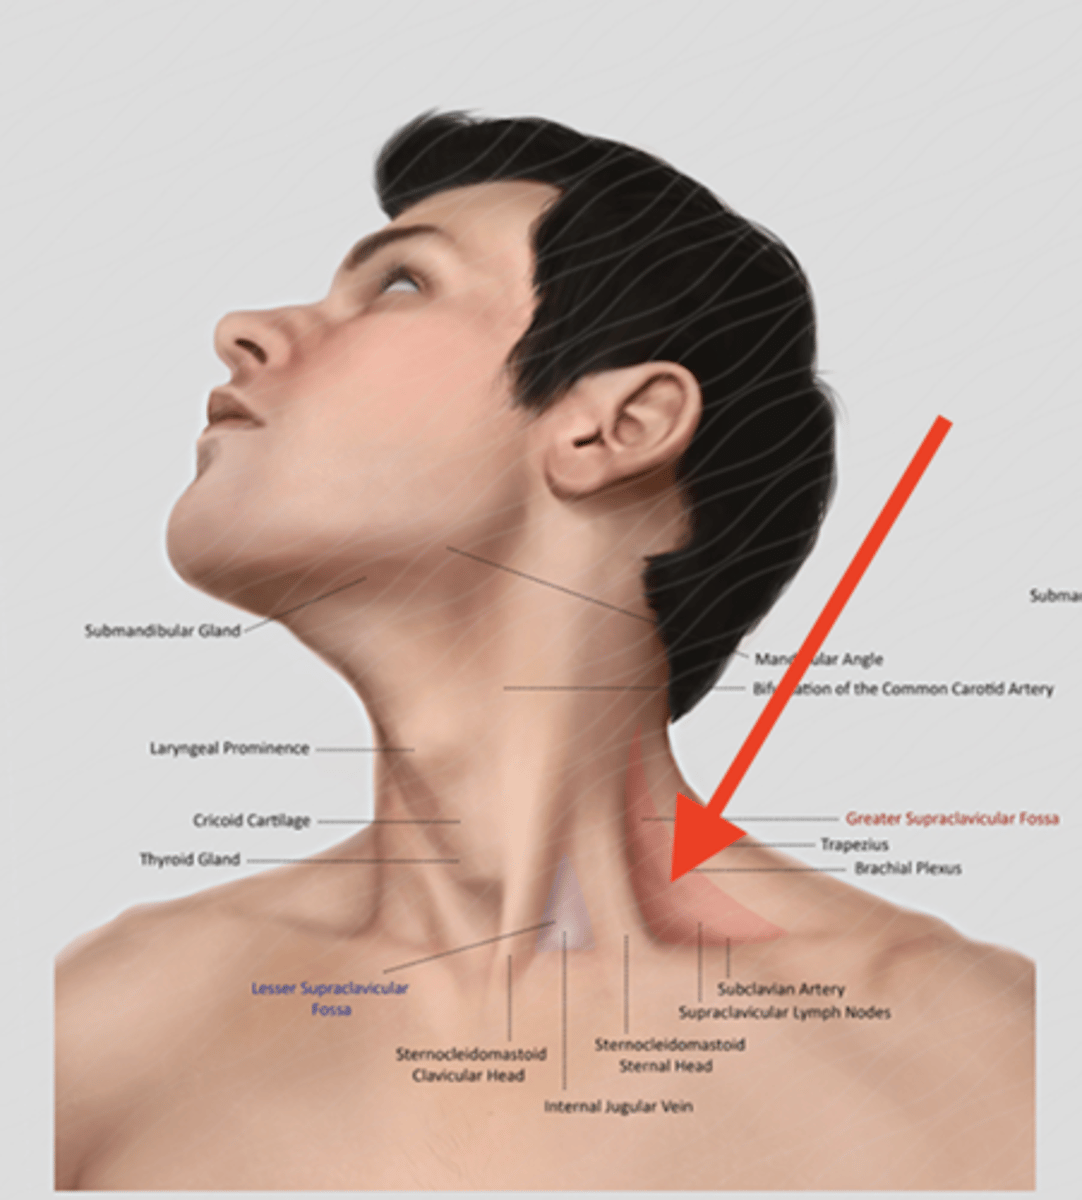

scalene muscles (surface anatomy)

name these muscles